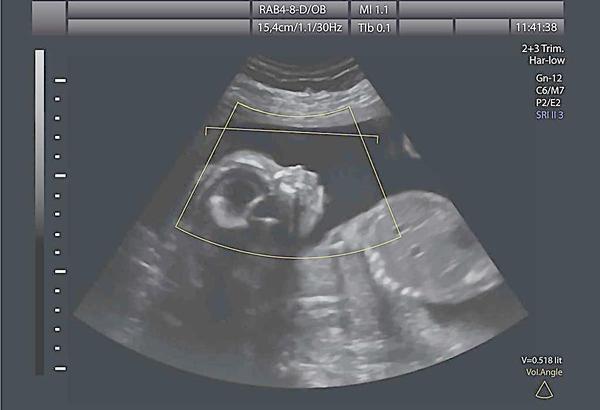

误区4:B超一定要少做,对胎儿不利。

医生解读:超声波和我们平时说话的声波一样,说话对人没有什么害处,超声波也一样,基本不会对人体产生影响。所以说超声波比较、不存在电离辐射和电磁辐射,使用起来也比较方便,成为现代医学中常用的影像学检查方法。

如果超声波的能量过大、使用时间过长会导致热应,这种热效应达到一定程度时,可能会对人体组织产生不良的影响,包括染色体。如果超声探头放在孕妈妈某一部位的时间过长,比如超过半小时甚至1小时,那就可能对胎儿有影响。但孕妈妈也不要担心,在医院做B超检查的时间一般不会超过这个时间,很少有长时间在一个部位检查的。因此,孕妈妈不可擅自减少B超检查的次数,要按医生的要求来做。